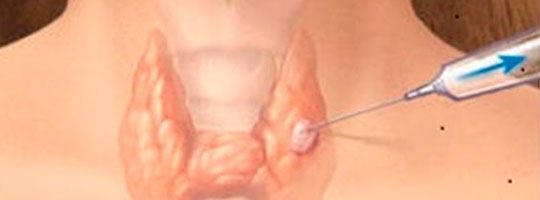

🔸 1. Punção aspirativa por agulha fina (PAAF)

Procedimento simples e rápido

Usa uma agulha fina para aspirar células do linfonodo

Pode ser feito em consultório ou com auxílio de ultrassom

Ideal para triagem ou lesões superficiais

Nem sempre fornece material suficiente para diagnóstico definitivo